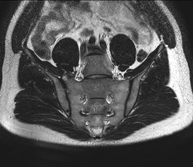

- Sacroiliac MRI

Study specifically designed to assess these joints and their inflammation in patients suffering from ankylosing spondylitis. It is also useful in patients with trauma and possible fractures of the sacrum and coccyx. It lasts approximately 16 minutes. It is a radiation-free procedure.

This non-invasive diagnostic procedure uses an electromagnetic field and radio waves (from a transmitter and receiver) to acquire high-definition anatomical images of the sacroiliac joints. It is a radiation-free procedure. Indicated for: inflammatory sacroiliac pain.